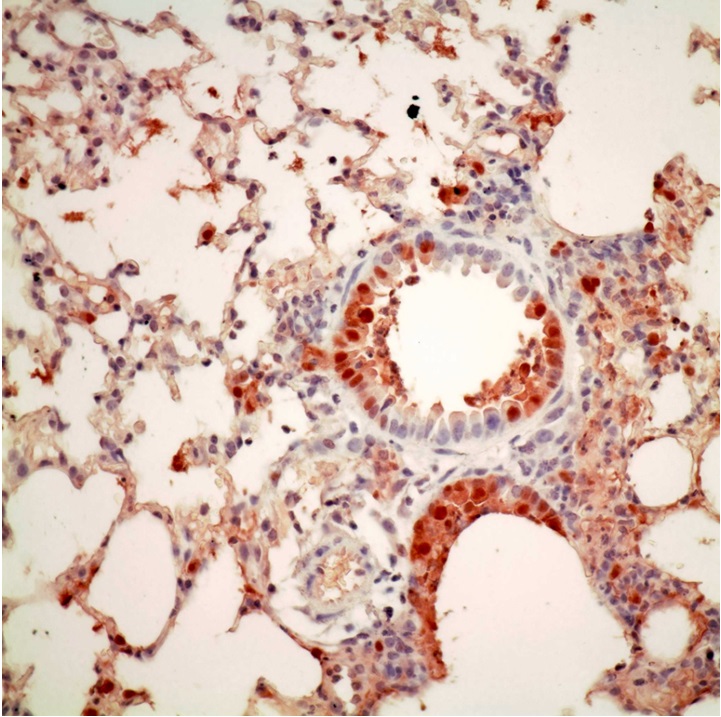

Host barriers block cross species transmission and replication of animal viruses in humans. Such host restriction mechanism limits the transmissibility and the ability of the avian virus to cause mammal and human infections. However, research team led by Dr. Honglin Chen, Associate Professor, and Professor Kwok-yung Yuen, Henry Fok Professor in Infectious Diseases, Chair Professor of Infectious Diseases from the Department of Microbiology, Li Ka Shing Faculty of Medicine, and State Key Laboratory for Emerging Infectious Diseases, the University of Hong Kong, found that avian influenza viruses may gain the ability to replicate in mammal and human cells through various adaptation changes in one of the viral replication complex subunits called the PB2, causing infections and diseases in humans. The discovery has been published recently in Nature Communications, in which team members Drs. Wenjun Song and Pui Wang are co-first authors.

In a recent study reported in the Nature Communications, a research team led by Dr. Honglin Chen, Associate Professor, and Professor Kwok-yung Yuen, Henry Fok Professor in Infectious Diseases, Chair Professor of Infectious Diseases from the Department of Microbiology, Li Ka Shing Faculty of Medicine, and State Key Laboratory for Emerging Infectious Diseases, the University of Hong Kong, found that avian influenza A H5N1 and H7N9, and seasonal H3N2 viruses may gain the ability to replicate in mammal and human cells through various adaptation changes in the viral replication enzyme complex called the PB2 subunit. They found that H7N9 avian influenza A virus is able to utilize multiple adaptive strategies to replicate in human cells, which may explain why H7N9 is distinct in causing human infections; This study identified a novel adaption marker, PB2-526R among some H7N9 viruses and almost exclusively among all H5N1 human cases from Indonesia. It has been a puzzle why there is no known PB2 adaptation marker in the H5N1 virus from Indonesia human cases and the finding from HKU nicely explained how this Indonesian subclade of avian H5N1 virus may have adapted for human infections. This study also found PB2-526R is able to enhance replication and pathogenicity of other types of PB2 adaptations, such as previously known PB2-627K, in H7N9 and H3N2 viruses. Since the human pandemic H3N2 virus emerged in 1968, it has gained an additional PB2-526R adaptation marker since 1970s and the PB2-526R-627K virus replicates better than the solely PB2-627K virus. It is likely that the impression of more severe disease burden caused by H3N2 than that of H1N1 may be partly attributed to the better replication ability of PB2-526R-627K virus. These findings by HKU provided new insight for the understanding of cross species transmission and replication in human cells by avian influenza viruses. The study provides a new genetic marker for the surveillance of avian influenza A virus with potential for human infection.